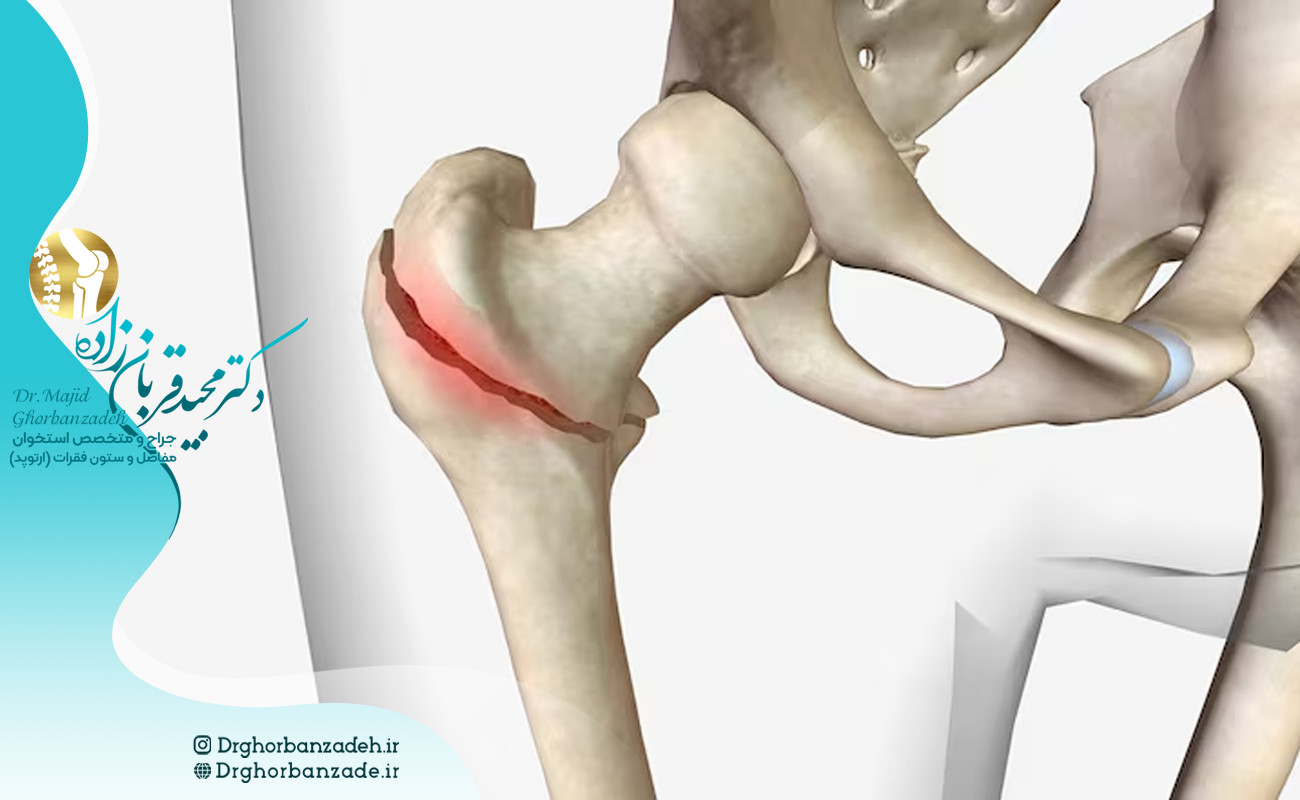

انواع مختلف شکستگی لگن

شکستگی لگن بسته به محل آسیب و شدت ضربه، در بخشهای مختلف استخوان لگن و ران رخ میدهد.

این آسیبها میتوانند شامل ترکهای مویی تا شکستگیهای کامل و جابهجاشده باشند.

در ادامه رایجترین انواع شکستگیهای لگن با توضیح هرکدام آورده شده است:

شکستگی گردن فمور (گردن استخوان ران)

شایعترین نوع شکستگی لگن است که در بخش گردن استخوان ران، درست زیر سر فمور اتفاق میافتد.

این نوع شکستگی بیشتر در سالمندان دیده میشود و در موارد شدید ممکن است سر استخوان ران نیز درگیر شود.